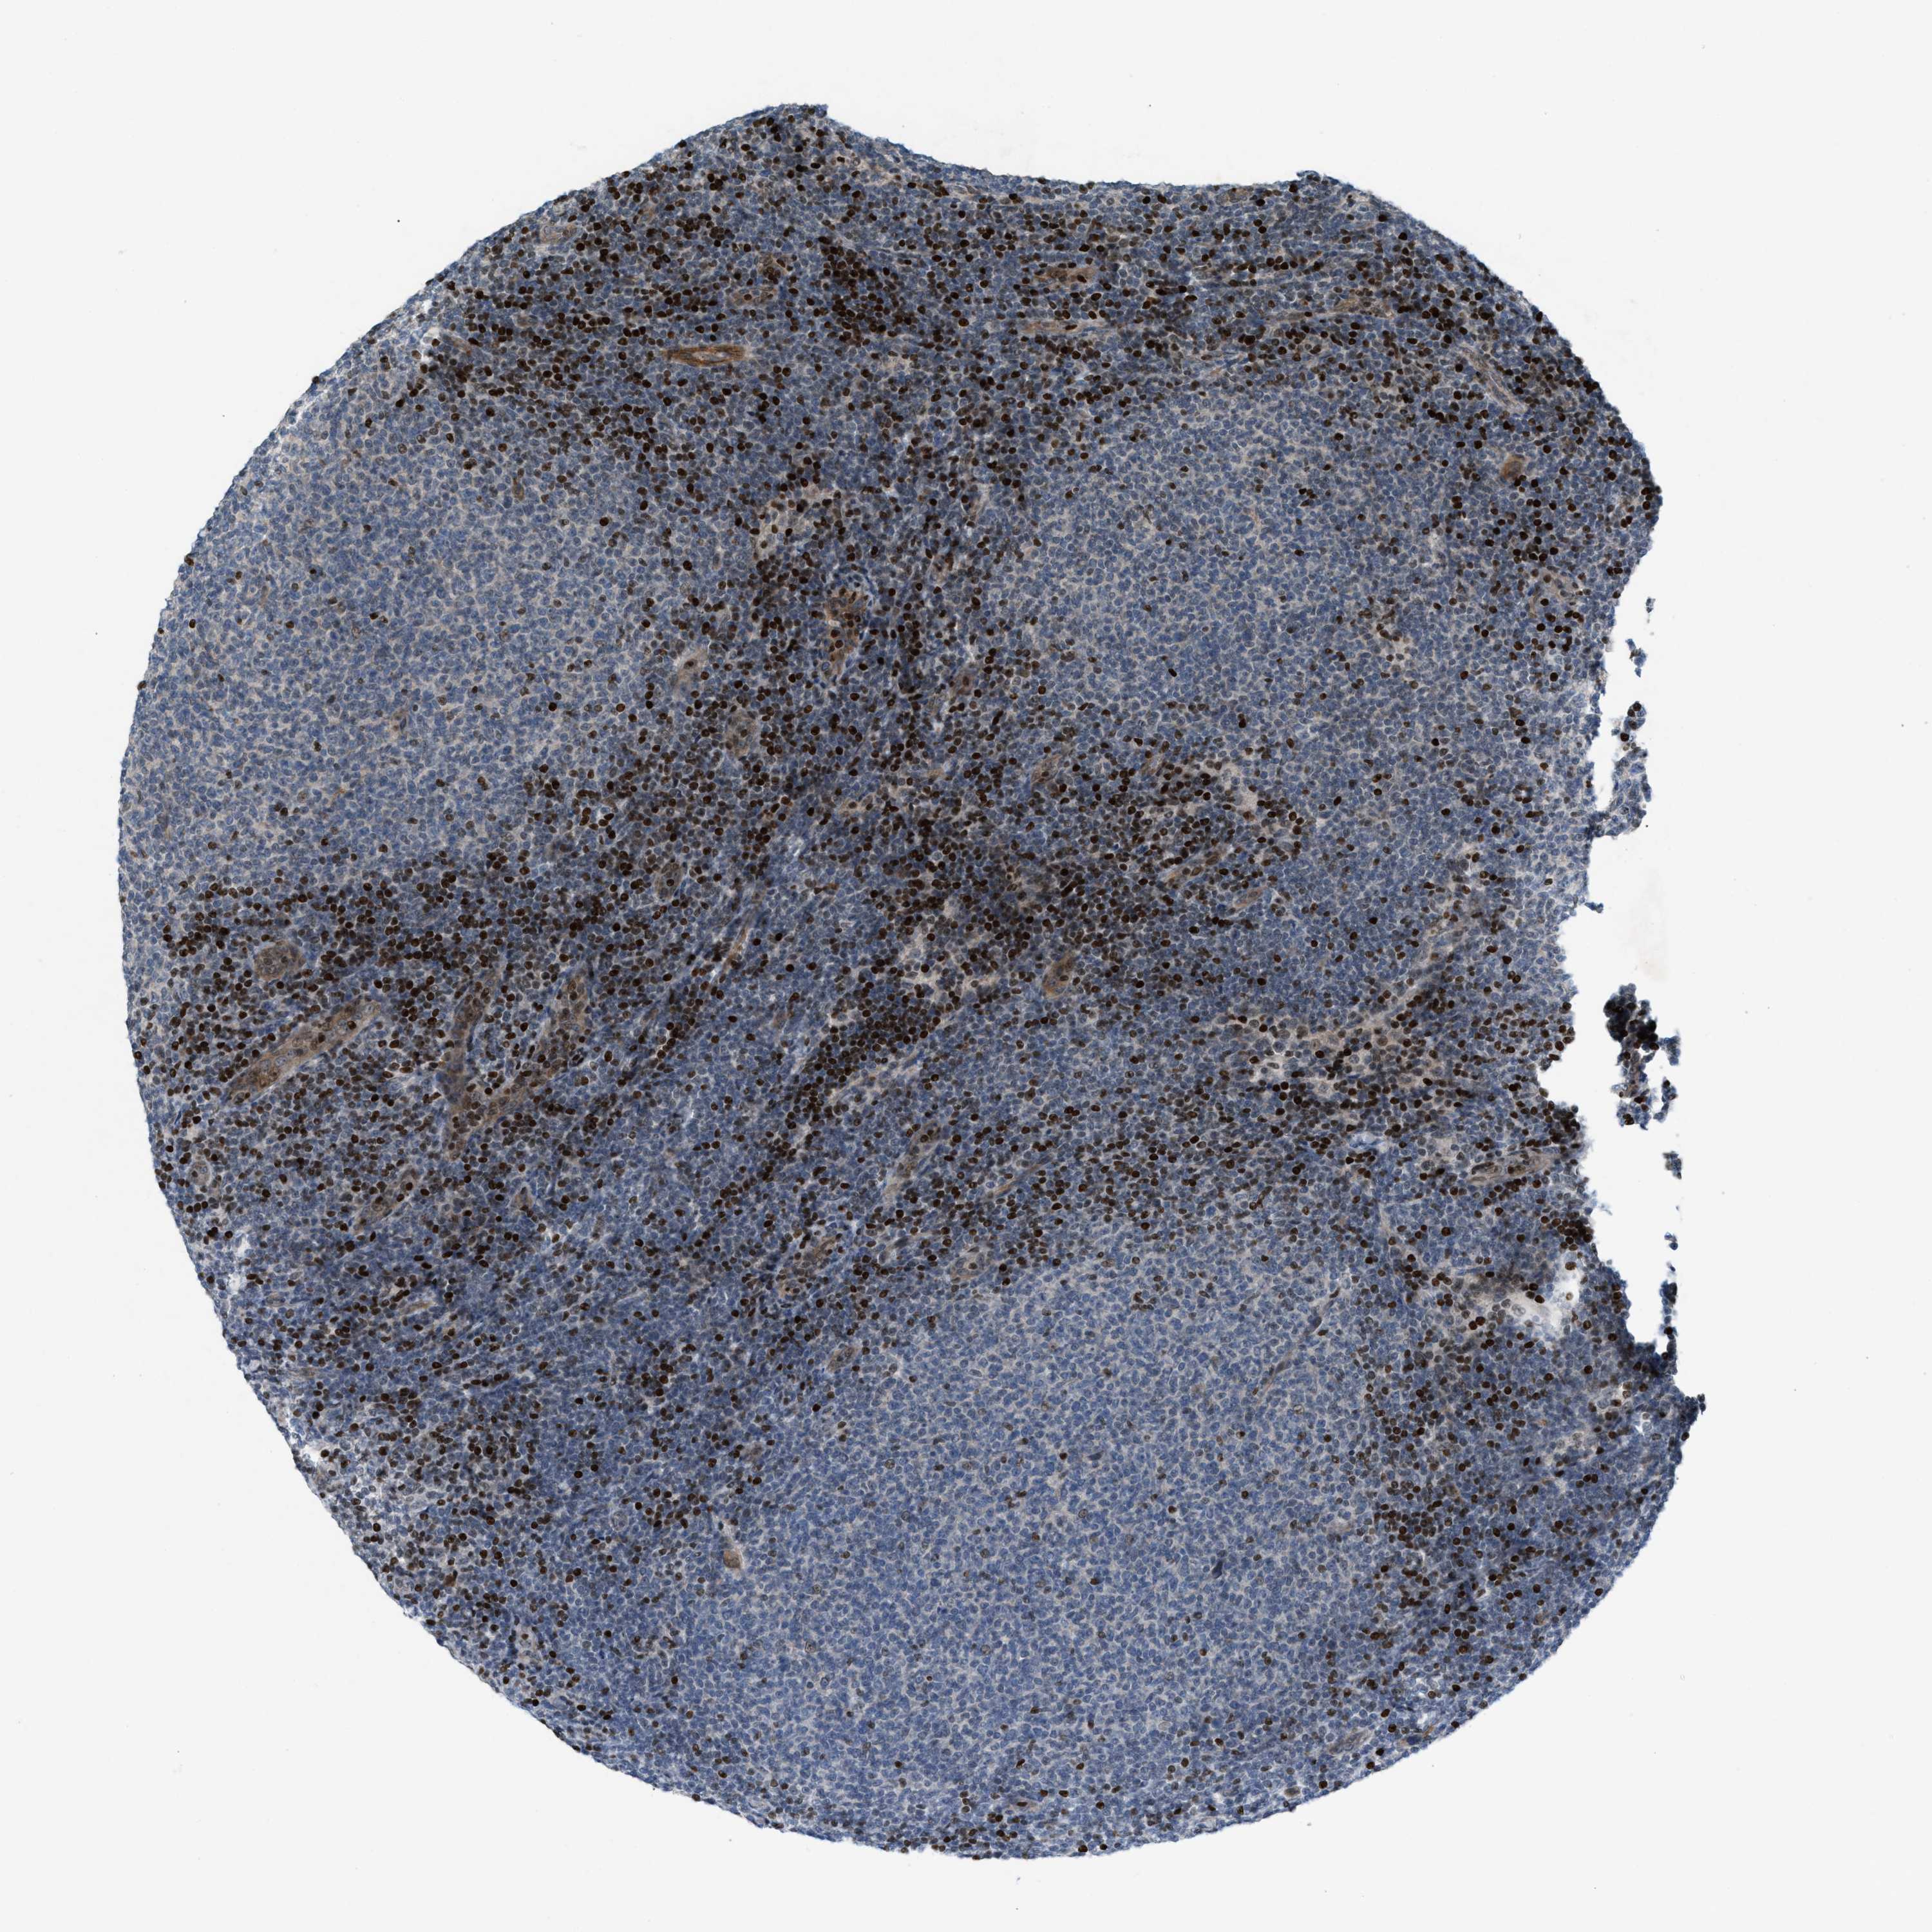

LYMPHOMA - Protein expressioni

A mouse-over function shows sample information and annotation data. Click on an image to view it in a full screen mode. Samples can be filtered based on level of antibody staining by selecting one or several of the following categories: high, medium, low and not detected. The assay and annotation is described here.

Antibody stainingi

Antibody staining in the annotated cell types in the current human tissue is reported as not detected, low, medium, or high, based on conventional immunohistochemistry profiling in selected tissues. This score is based on the combination of the staining intensity and fraction of stained cells.

Each image is clickable and will lead to virtual microscopy that enables deeper exploration of all samples and also displays staining intensity scores, fraction scores and subcellular localization as well as patient and tissue information for each sample.

Antibody HPA021309

Antibody HPA022255

Staining

High

Medium

Low

Not detected

Intensity

Strong

Moderate

Weak

Negative

Quantity

>75%

75%-25%

<25%

None

Location

Nuclear

Cytoplasmic/membranous

Cytoplasmic/membranous,nuclear

Hodgkin's disease, NOS

Malignant lymphoma, non-Hodgkin's type, High grade

Malignant lymphoma, non-Hodgkin's type, Low grade